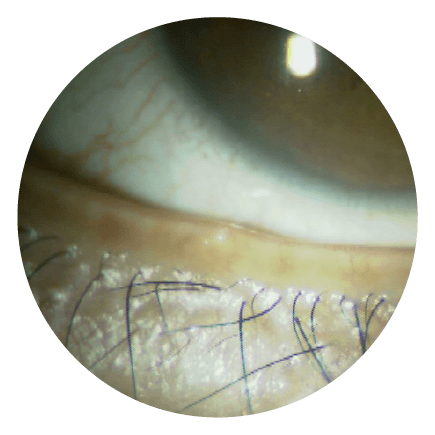

04 圧出前の下眼瞼の様子

マイボーム腺機能不全の部分が盛り上がっています

05 圧出

マイボーム腺圧迫セッシでマイボーム腺のつまりを解消します

06 圧出され汚れた脂分

詰まっていた脂分が出てきます